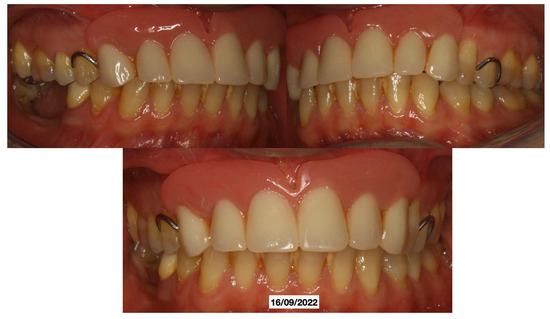

It was decided to temporarily rehabilitate the edentulism with a fixed partial denture after preparing 23-12-13 (Figure 4), keeping the adjacent teeth under observation but with a slight radiolucency already present.

Just two weeks later, a rapid worsening was observed (documented with periapical intraoral X-rays) of the elements (13-12-23), which led to their necessary extraction (May 2022), with decontamination of the alveoli, with the beginning of a reabsorption process involving 14-15-16-46-47 (March 2022) with delivery of a removable partial prosthesis (Figure 5).

Figure 5. Removal partial prosthesis.